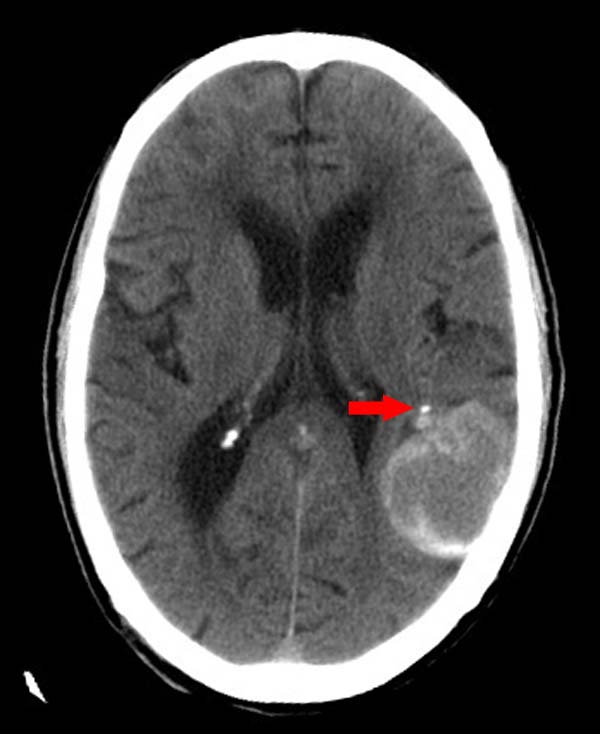

左颞枕叶交界区可见类圆形高密度区,边缘可见环形更高密度影,并夹杂有点状钙化影,占位效应明显,未见明显水肿影,考虑脑膜瘤出血

左颞枕叶交界区可见类圆形高密度区,边缘可见环形更高密度影,侧脑室后角明显受压而周围未见明显水肿.考虑脑膜瘤伴出血可能性大不排外血管畸形.建议mr进一步检查.

左侧颞枕叶交界区见类圆型等高密度混杂影,边缘可见高密度影环绕,同侧侧脑室后脚受压变形,周边围见明显水肿影. 结论:脑膜瘤首先考虑.

左颞枕叶交界区的类圆形高密度区首先考虑脑膜瘤卒中,病人左侧小脑半球的还有多个囊性低密度,要考虑同时伴有梗塞的可能。

这个病人做ct时已经10小小时了,按说出血多稳定了,这么少的出血和这么小、少的梗塞怎么会导致病人昏迷?而脑干、脑桥和中脑都没有发现出血或梗塞,也没有明显的颅内高压,真的很奇怪。